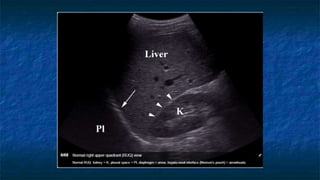

FAST: RUQ exam

 Normal Anatomy

 In the supine patient, the

hepatorenal space

(Morison’s Pouch) is the

most dependent space

Anterior

Posterior

Inferior

Superior

Morison’s

Pouch